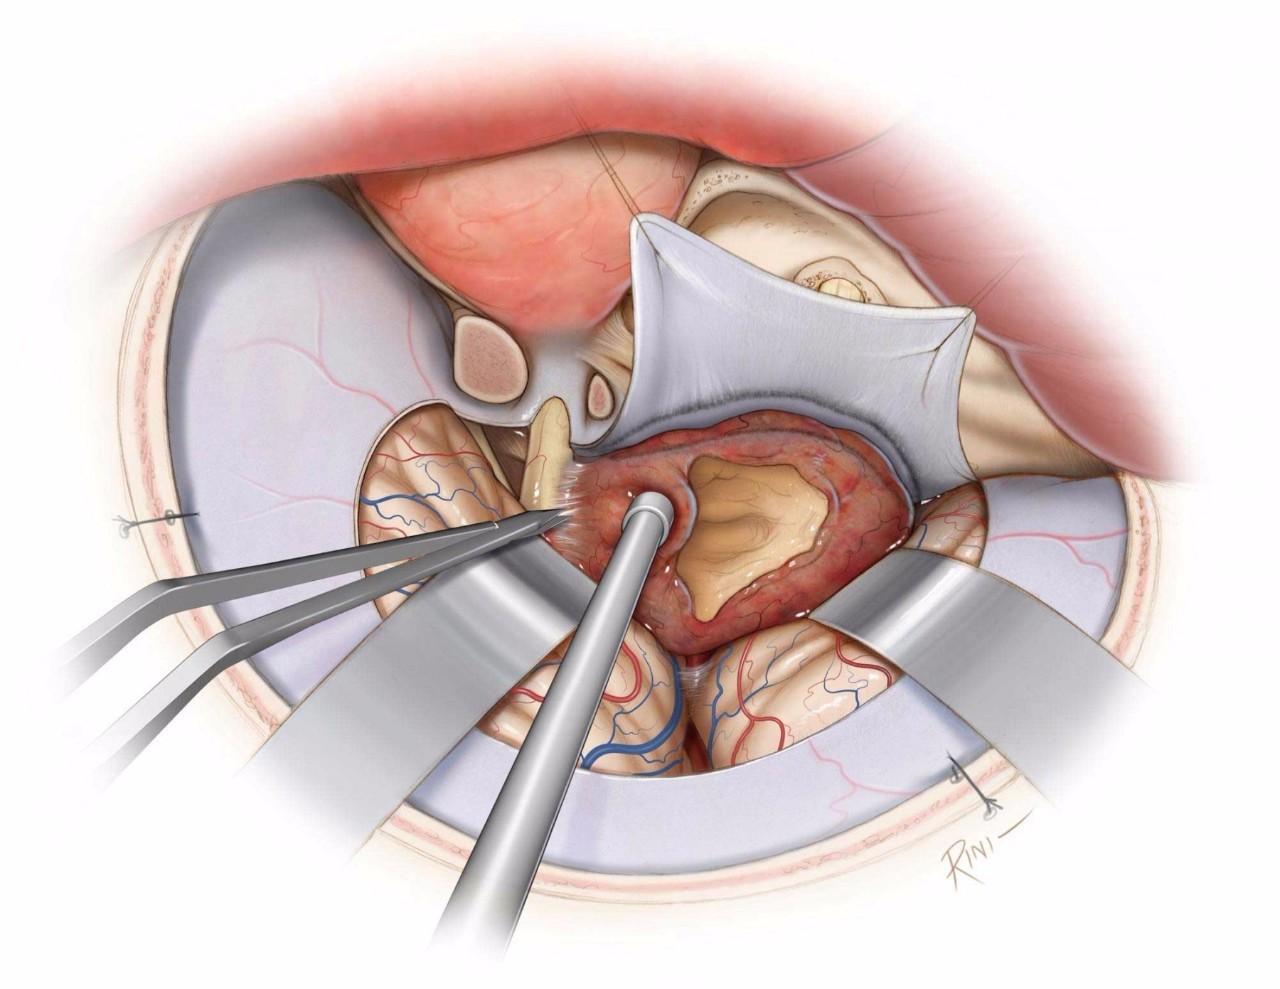

图8:对海绵窦周围区域的暴露,可通过眶颧开颅或扩大翼点开颅,结合硬膜外前床突切除术即眶后部切开术来实现。对于硬膜内入路,首先切除肿瘤的窦外部分,并在早期切开镰状韧带实现视神经减压。可沿蝶骨翼内侧的硬膜去除肿瘤窦外部分的血供。开放三叉神经出颅的骨孔,可暴露侵入这些骨孔的肿瘤。

图9:先处理累及视神经的肿瘤,以免在之后的操作中损伤视神经。将肿瘤包膜从视神经上锐性剥离下来。注意保护神经下表面的穿通动脉。注意处理肿瘤基底以减少血供,并尽可能彻底的瘤内减压。使用固定牵开器适当牵开额叶和颞叶以对其进行保护。

图10:继续将肿瘤包膜与视神经颈内动脉池内各神经血管结构相分离。该阶段最容易损伤的神经为滑车神经,可于天幕游离缘辨认并追踪其入海绵窦内。紧密粘连于神经的肿瘤碎片,应避免强行切除,以保留神经功能。穿通动脉也应予以保护。